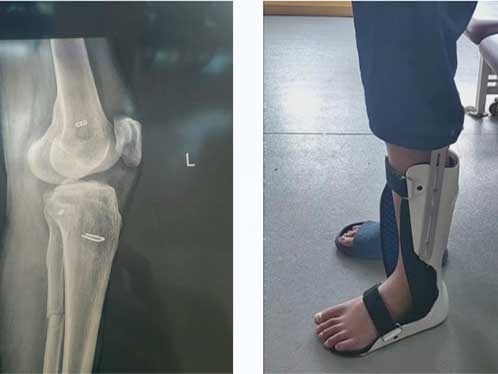

優(yōu)勢技術(shù)|關(guān)節(jié)術(shù)后配合康復(fù)訓(xùn)練 恢復(fù)最佳狀態(tài)事半功倍

前交叉韌帶損傷術(shù)后康復(fù)訓(xùn)練扮演著非常重要的角色!這些訓(xùn)練包括肌力、平衡和功能性訓(xùn)練等,有助于逐漸恢復(fù)膝關(guān)節(jié)周圍肌肉力量和控制力,提高關(guān)節(jié)穩(wěn)定性。同時,康復(fù)訓(xùn)練還能加速受損組織的修復(fù)和再生,預(yù)防再次損傷。